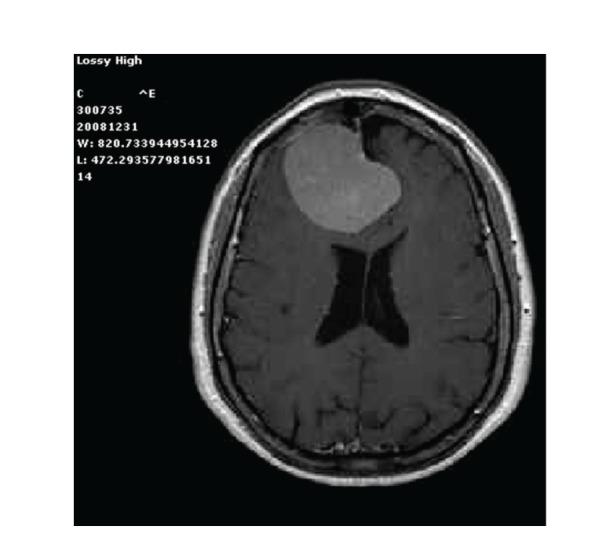

Background. Numerous reports have demonstrated how postoperative intracranial granulomas can often mimic neoplasm clinically, radiologically, and even macroscopically. Herein we present an unusual case of postsurgical intracranial aseptic granuloma secondary to a chronic inflammatory reaction without any identifiable retained foreign body. Case Description. A 71-year-old patient started complaining of severe headache seven months after surgical excision of WHO Grade I right frontal falx meningioma. CT and MRI scans disclosed a contrast-enhanced lesion with diffuse mass effect in the previous surgical site. The lesion was resected; intraoperative finding and histological specimens led to the diagnosis of postoperative granuloma, likely expression of a glial reaction to the fluid absorbable hemostatics applied in the surgical site after meningioma excision. The possible granuloma-inducing materials and the timing of granuloma formation are discussed. Conclusion. A comprehensive analysis of clinical and neuroradiological data, as well as results of blood tests including positive and negative acute phase proteins, is mandatory to raise the suspicion of postoperative granuloma. The treatment options should be evaluated on a case-by-case basis, with a conservative attitude being the one of choice only for patients without progressive neurological deficit. Alternatively, aggressive surgical treatment and histopathological examination should be advocated.

背景。大量报告表明,术后颅内肉芽肿在临床、放射学甚至宏观层面上常常可模拟肿瘤。在此,我们呈现一例不寻常的术后颅内无菌性肉芽肿病例,其继发于慢性炎症反应,且无任何可识别的残留异物。病例描述。一名71岁患者在世界卫生组织一级右额镰旁脑膜瘤手术切除七个月后开始主诉严重头痛。CT和MRI扫描显示在先前手术部位有一个强化病变,伴有弥漫性占位效应。该病变被切除;术中发现及组织学标本诊断为术后肉芽肿,可能是对脑膜瘤切除后手术部位应用的可吸收液体止血剂的胶质反应表现。讨论了可能诱发肉芽肿的物质及肉芽肿形成的时间。结论。对临床和神经放射学数据以及包括正负急性期蛋白在内的血液检查结果进行全面分析,对于提高对术后肉芽肿的怀疑至关重要。治疗方案应逐案评估,对于无进行性神经功能缺损的患者,保守态度是首选。或者,应提倡积极的手术治疗和组织病理学检查。